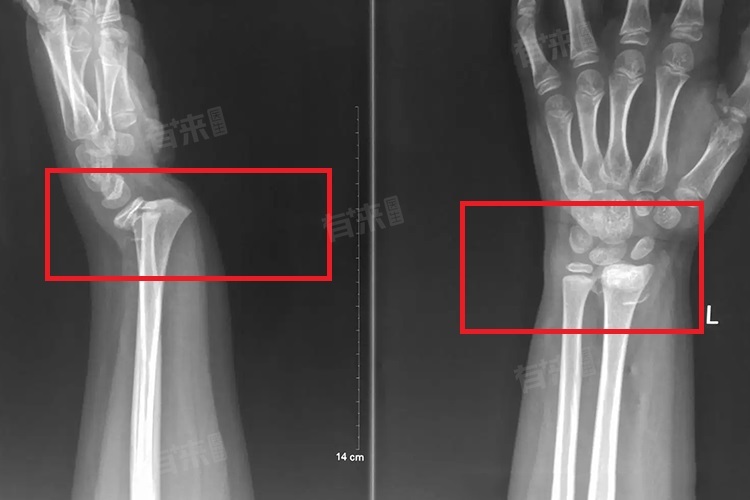

4、肢体畸形:当骨折移位较为严重时,可以看到或感觉到受伤肢体形状的变化,比如变短、旋转或者成角畸形。这是骨折未能对齐的结果,不仅影响外观,更重要的是干扰了正常的生理功能。

- 手法复位:对于骨折移位程度较轻、骨折断端较整齐的情况,医生多采用手法复位。通过牵引、推挤、旋转等手法,凭借经验与手感,精准调整骨折断端位置,使其恢复正常或接近正常解剖关系,随后配合固定措施,保障复位效果。

- 手术切开:若骨折移位严重,手法复位难以实现,如粉碎性骨折、累及关节面的骨折等,需手术切开。在直视下清理骨折处,用钢板、螺钉、髓内钉等内固定物,牢固固定骨折断端,精准恢复骨骼形态,促进骨折愈合。